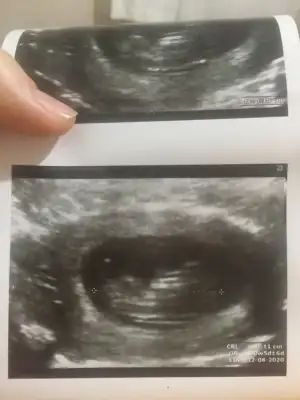

Net degil usg 11+ yada 12+ oldugunda paylaşın yada net varsa usg paylaşın

mrhaba lütfen yorumlarmisiniz sizce kızmı erkekmi bi arkadas icin soruyorum

Sevgili İkra,

Yorumlarsan çok sevinirim. ☺️❤️